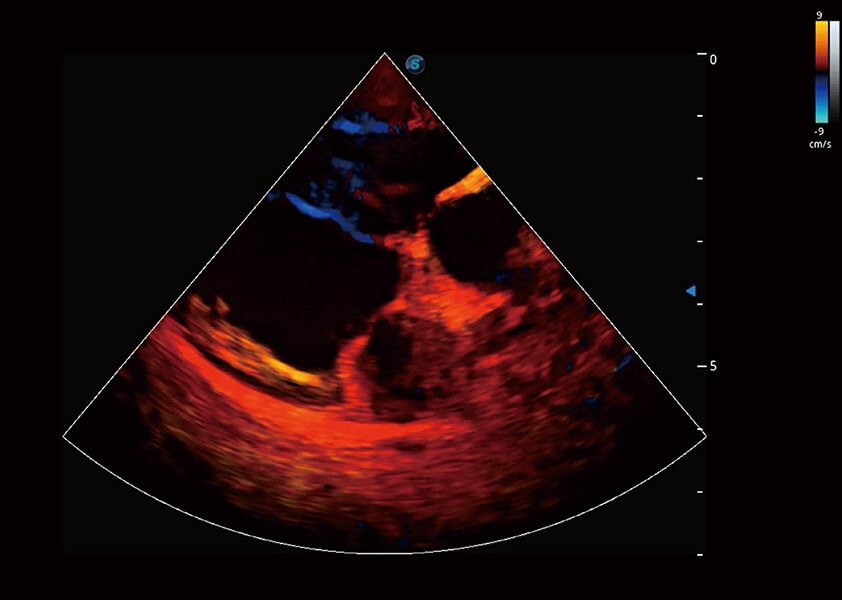

心脏解决方案

ProPet 60 配备了丰富的心脏探头群、先进的成像技术和专业的心脏测量工具,可帮助动物医生为不同体型和生理结构的动物提供心脏和心肌功能的全面评估。

• TDI 组织多普勒成像

实时用颜色表示心肌组织运动,观察和定量组织的运动情况,对快速检测与评估心肌的灌注和活性、电传导及心肌收缩和舒张功能等均能提供重要的诊断信息。

优异的基础图像

(犬)四腔心血流

(犬)心脏组织多普勒